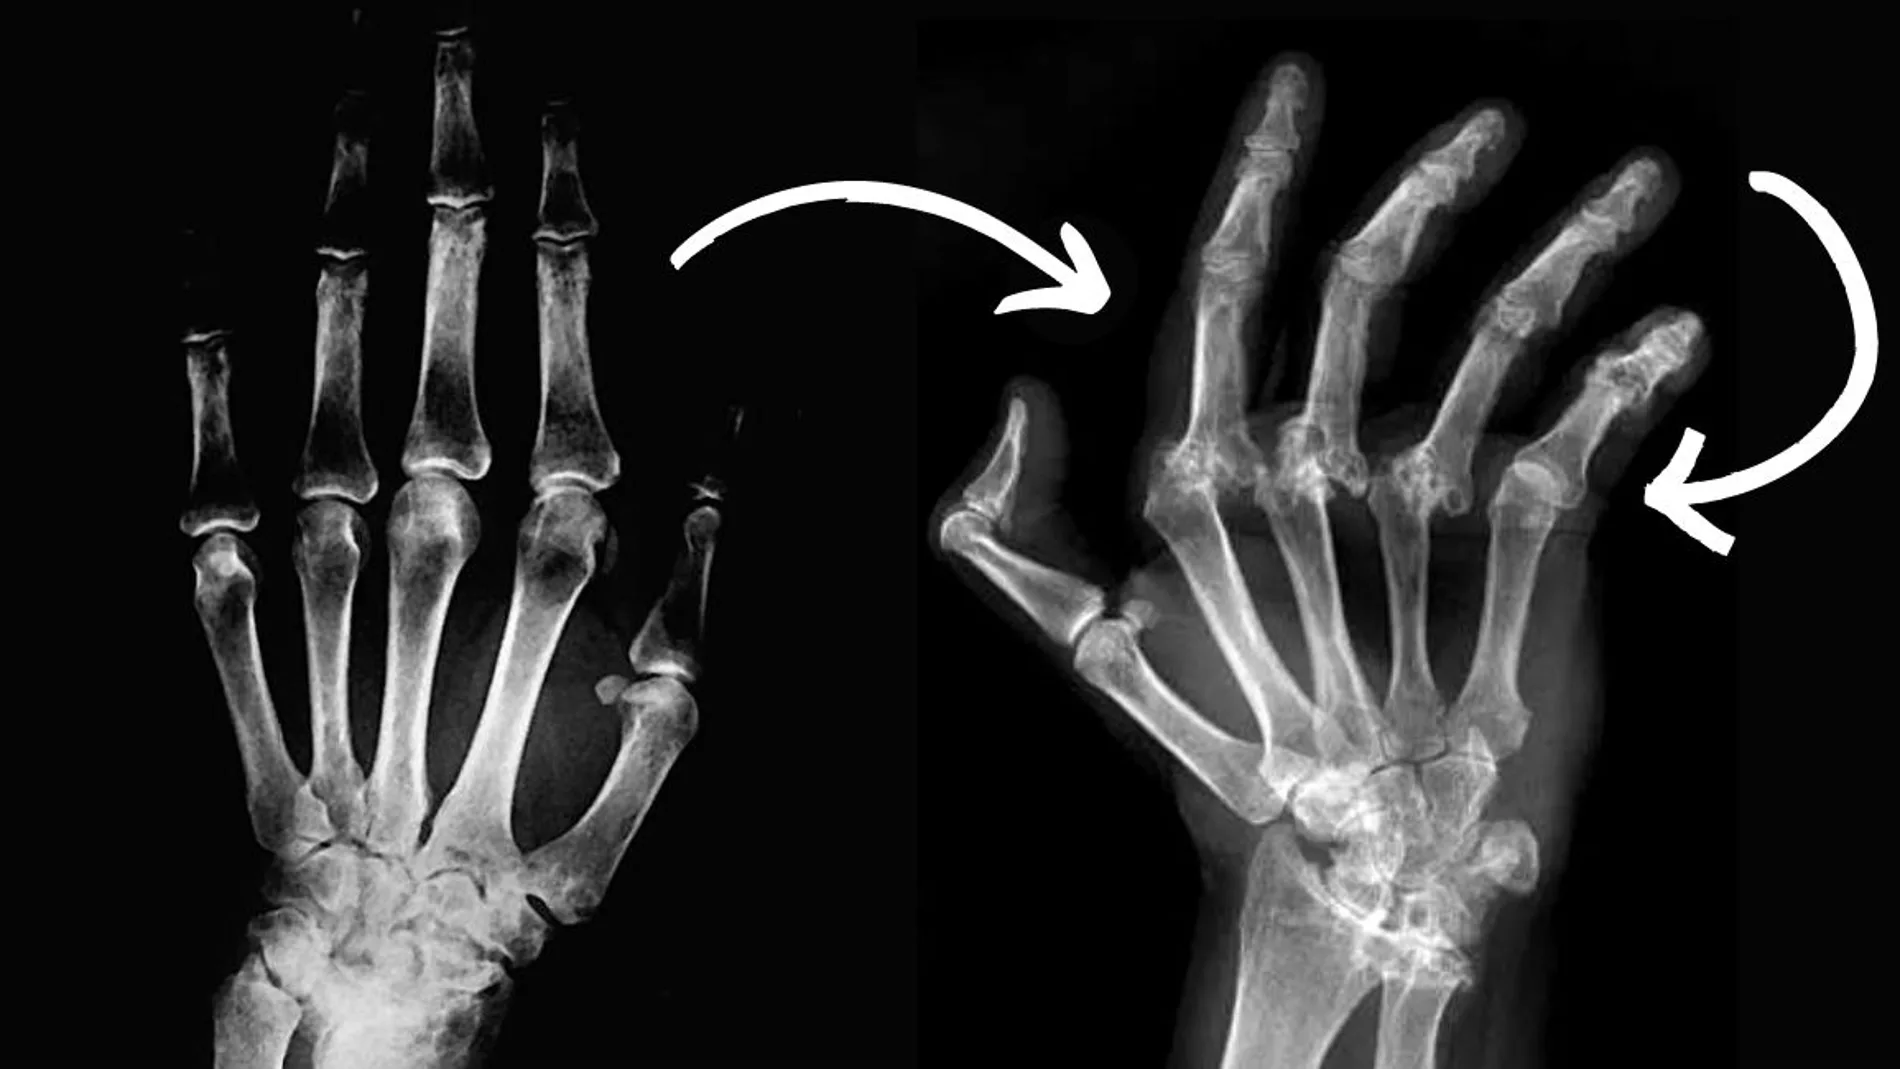

Ahora, una nueva dolencia se añade a la lista de daños físicos asociados a las PAH. Así lo confirma un nuevo estudio publicado en la prestigiosa revista BMJ Open, que ha encontrado que la exposición directa o indirecta a la contaminación causada por la quema de materiales, productos químicos o subproductos de la preparación alimentaria aumenta el riesgo de sufrir enfermedades autoinmunitarias, especialmente la artritis reumatoide. España, en donde el consumo de carne es de alrededor de 50 kilos por persona al año y los casos de artritis aumentan, se vería especialmente afectado.

De acuerdo con los hallazgos, los participantes con mayores niveles de HAP en sus organismos presentaron mayores probabilidades de sufrir artritis reumatoide, independientemente de si eran fumadores o exfumadores. Y es más: al comparar las personas en el cuartil más alto de carga corporal de HAP con las del cuartil más bajo, las probabilidades de desarrollar AR eran más del doble. Además, un tipo de HAP, el 1-hidroxinaftaleno, se relacionó específicamente con un mayor riesgo de desarrollar artritis reumatoide.